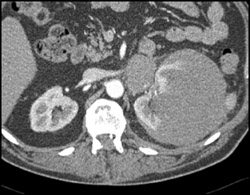

Nephroblastomatosis